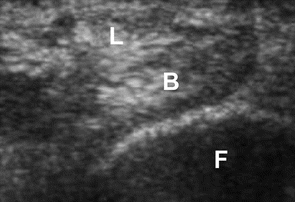

动态超声允许实时评估脱位时腓骨肌腱的异常运动,特别是配合踝关节内翻、跖屈位背伸、外翻活动,有助于发现 CT 和 MRI 假阴性静态成像结果。

患肢踝关节处于中立位时获得的轴位超声图显示腓骨远端 (F) 后方的腓骨长肌 (L) 和腓骨短肌 (B) 肌腱处于正常关系。图源:DOI:10.2214/ajr.183.4.1830985

患肢踝关节背伸外翻的轴位超声图显示腓骨长肌 (L) 和腓骨短肌 (B) 脱位,位于腓骨远端 (F) 浅表。图源:DOI:10.2214/ajr.183.4.1830985